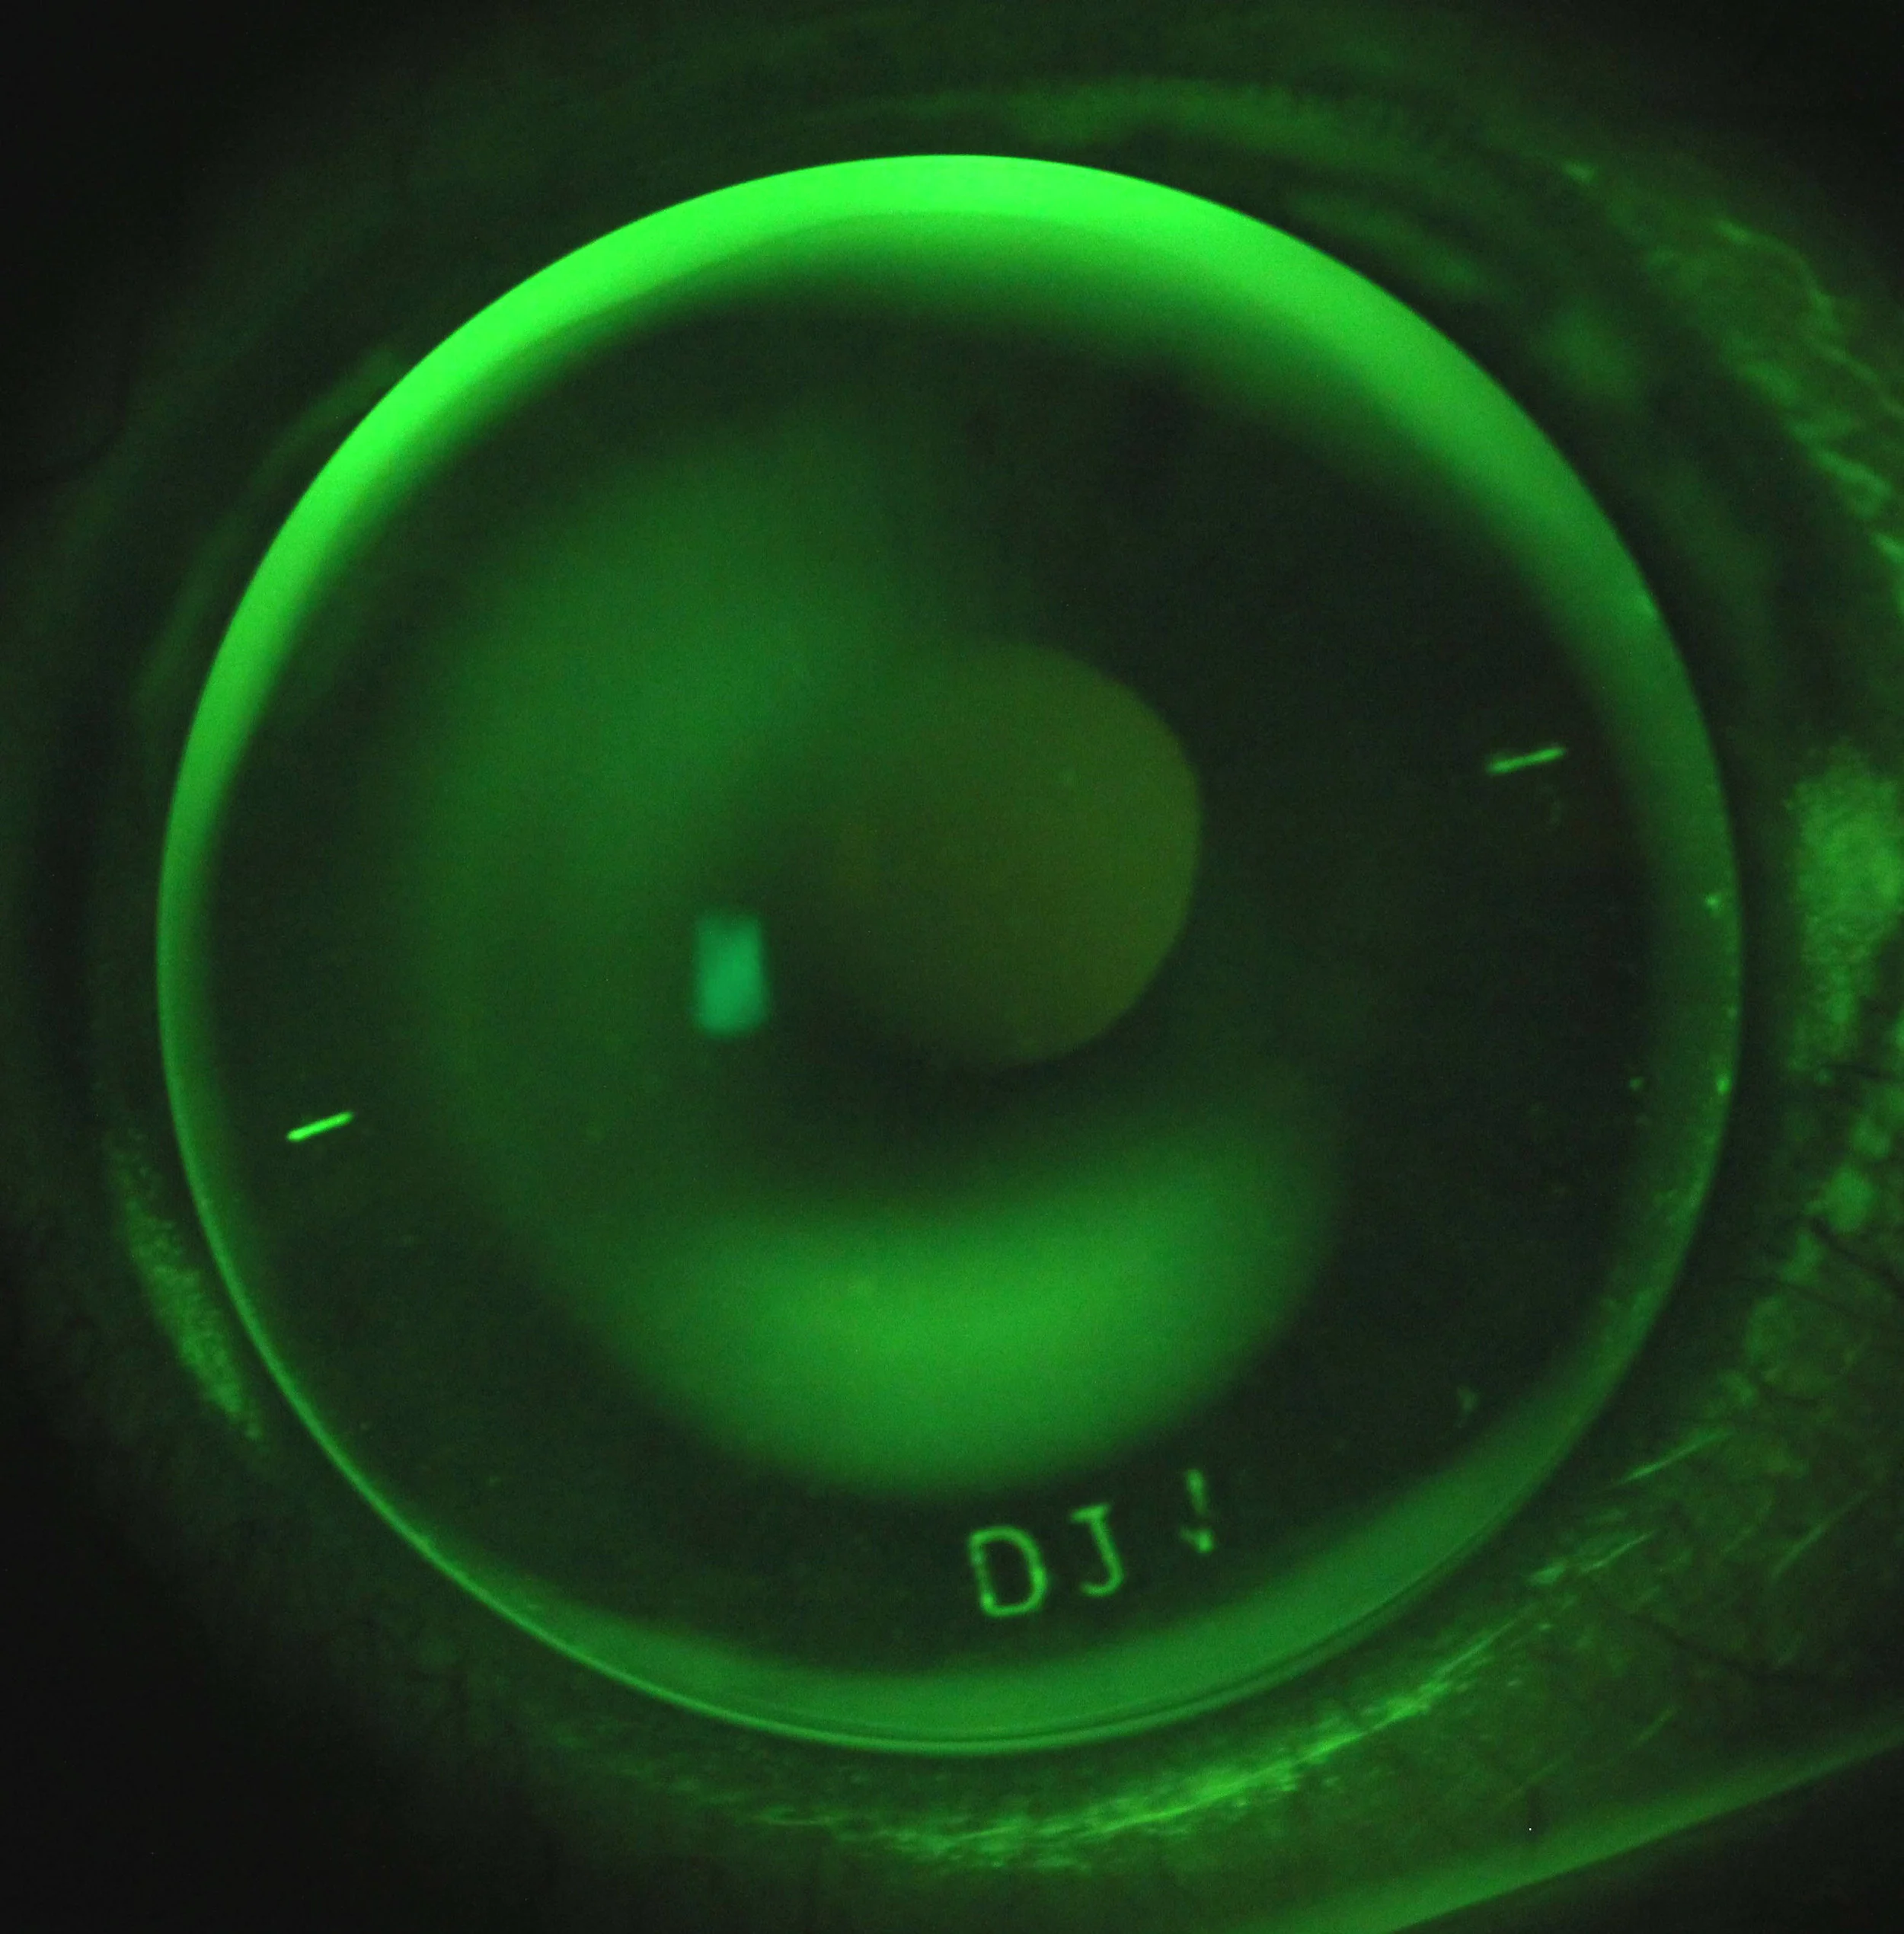

From www.eyenews.uk.com

Advances in the understanding, diagnostic and treatment of keratoconus Eye Drops For Keratoconus this study provides the first evidence that altered corneal epithelial and stromal expression of specific genes at the corneal cone apex drives. In almost all cases, glasses or a contact lens are necessary to. In 2020, under the leadership of iveena, a team of researchers evaluated the safety and preliminary efficacy of the eye drops in phase i. Eye Drops For Keratoconus.